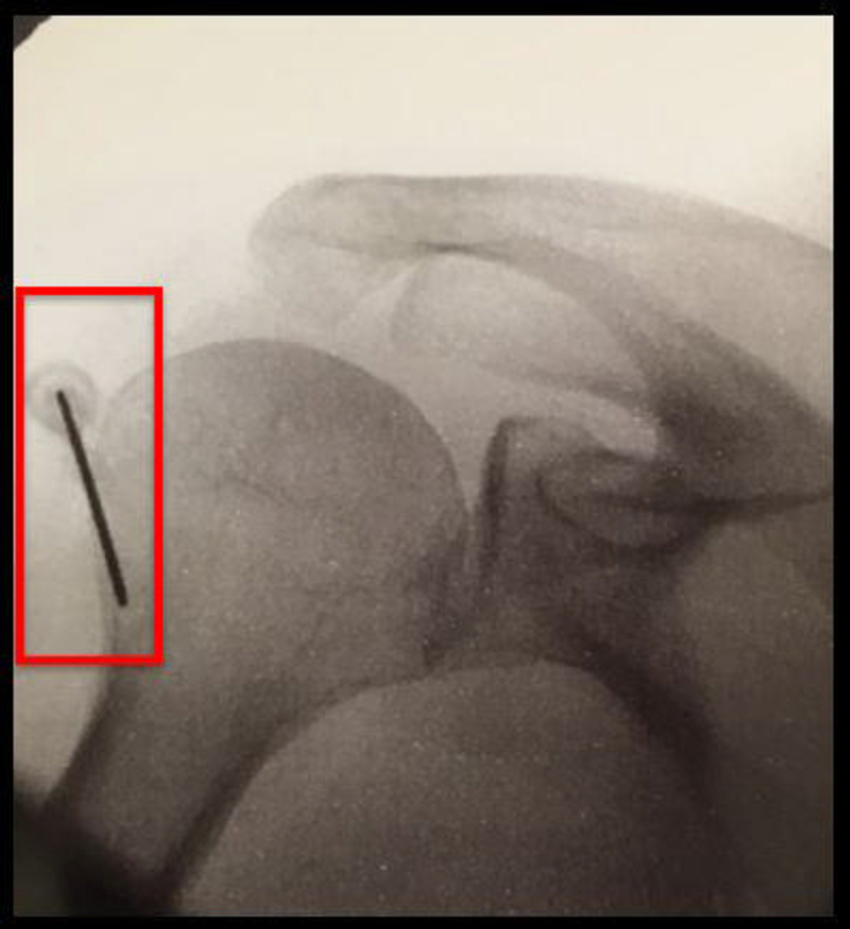

Figure 3. Shoulder-specific technique: there are five ablation targets

High-res (TIF) version

Figure 4. Suprascapular nerve cooled radiofrequency ablation targets.

Figure 5. Suprascapular nerve cooled radiofrequency ablation: Target #1

Figure 7. Axillary nerve cooled radiofrequency ablation: ablation targets.

Figure 8. Axillary nerve cooled radiofrequency ablation: Ablation target #3.